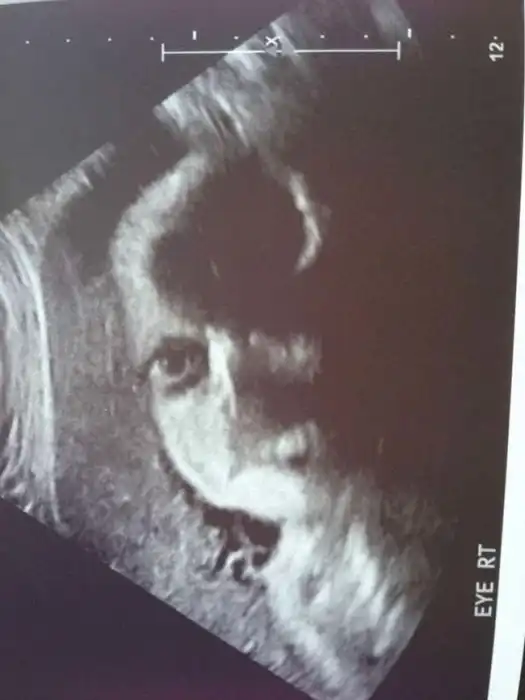

Как выглядят дети в утробе матери на экранах аппаратов УЗИ

На экранах аппаратов УЗИ дети, находящиеся в утробе матери, выглядят далеко не такими милыми и симпатичными, какими они оказываются после своего рождения.